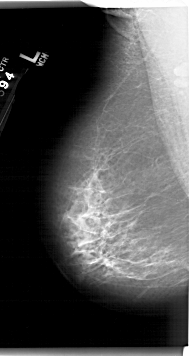

A_1411_1.LEFT_CC

LEFT_CC LINES 6571 PIXELS_PER_LINE 3451 BITS_PER_PIXEL 12 RESOLUTION 43.5 NON_OVERLAY